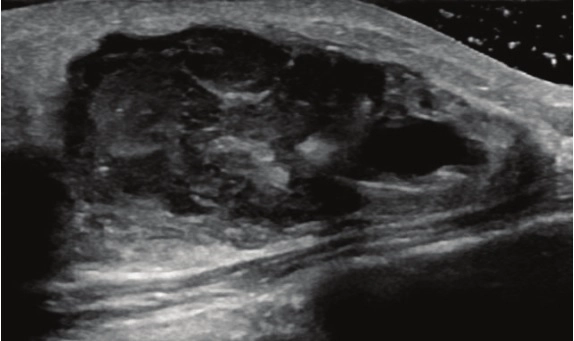

• Tuyến vú